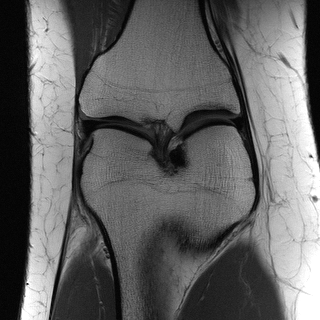

This article presents a novel undersampled magnetic resonance imaging (MRI) technique that leverages the concept of Neural Radiance Field (NeRF). With radial undersampling, the corresponding imaging problem can be reformulated into an image modeling task from sparse-view rendered data; therefore, a high dimensional MR image is obtainable from undersampled $k$-space data by taking advantage of implicit neural representation. A multi-layer perceptron, which is designed to output an image intensity from a spatial coordinate, learns the MR physics-driven rendering relation between given measurement data and desired image. Effective undersampling strategies for high-quality neural representation are investigated. The proposed method serves two benefits: (i) The learning is based fully on single undersampled $k$-space data, not a bunch of measured data and target image sets. It can be used potentially for diagnostic MR imaging, such as fetal MRI, where data acquisition is relatively rare or limited against diversity of clinical images while undersampled reconstruction is highly demanded. (ii) A reconstructed MR image is a scan-specific representation highly adaptive to the given $k$-space measurement. Numerous experiments validate the feasibility and capability of the proposed approach.